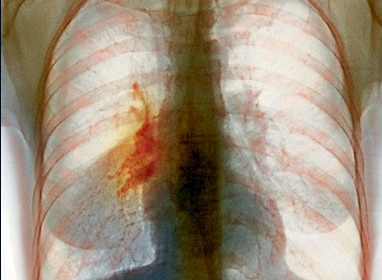

Злокачественный процесс представляет собой неконтролируемый рост аномальных клеток в одном или обоих легких. Мутированные клетки не выполняют своих функций. Кроме этого, патологический рост опухоли повреждает легочную структуру. Как следствие – легкие теряют способность обеспечивать организм кислородом.

Врачи отмечают, что рак правого легкого является одной из наиболее распространенных форм онкологических заболеваний. По их мнению, ранняя диагностика играет ключевую роль в успешном лечении. Специалисты подчеркивают важность регулярных медицинских осмотров, особенно для людей с факторами риска, такими как курение или наследственная предрасположенность.

- Рак правого легкого.

- Периферический рак правого легкого на ранних стадиях протекает практически бессимптомно. Такая форма заболевания диагностируется случайно (при проведении рентгенологического обследования органов грудной клетки) или целенаправленно (на поздних стадиях протекания болезни, когда проявляется ее общая симптоматика).